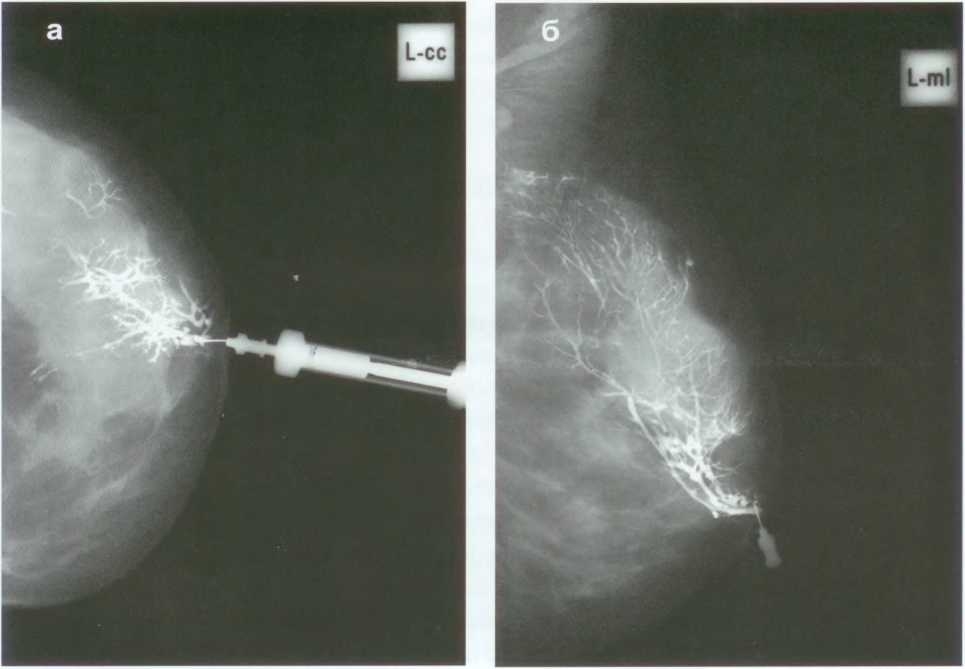

Второй этап исследования – маммография. Пациентка укладывает грудь на специальную подставку маммографа, сверху грудные железы придавливаются пластиной. Далее производится съемка – сверху и сбоку. Это позволяет получить снимки в двух проекциях (вертикальной и косой) и лучше рассмотреть подозрительные участки. На этом дуктография считается оконченной.

Изучением снимков, полученных в ходе дуктографии, занимает врач-рентгенолог. Он может обнаружить:

Кроме того, врач обязательно оценивает, на каком расстоянии от соска локализуются патологические изменения, в каком состоянии разветвления млечных проток. На основании всей увиденной информации он может предположить, какое заболевание развивается у пациентки.